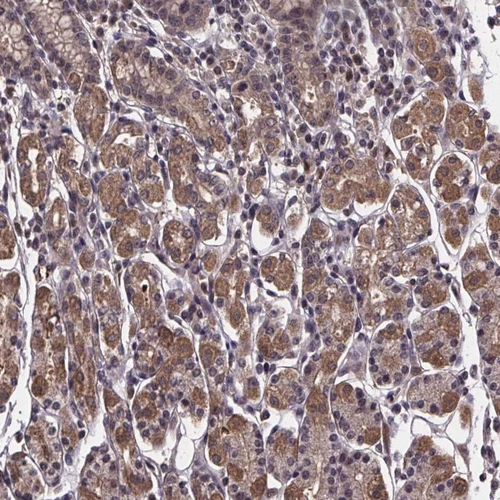

Immunohistochemical staining of human stomach shows moderate cytoplasmic positivity in glandular cells.